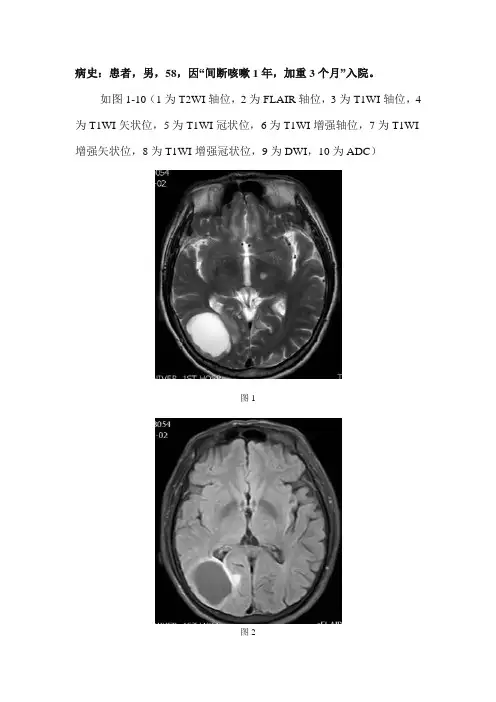

病史:患者,男,58,因“间断咳嗽1年,加重3个月”入院。

如图1-10(1为T2WI轴位,2为FLAIR轴位,3为T1WI轴位,4为T1WI矢状位,5为T1WI冠状位,6为T1WI增强轴位,7为T1WI 增强矢状位,8为T1WI增强冠状位,9为DWI,10为ADC)图1图2图3图4图5图6图7图8图9图10基础解剖影像:图11图12图13图14图15图11-15为正常人颅脑主要层面T2WI轴位图片图11为中脑层面,主要包括中脑(黄色箭头),前方为桥前池(棕色箭头),后方为第四脑室(蓝色箭头),颞叶(绿色箭头),小脑半球(白色箭头)。

图1图2图3图4图5图6图7图8图9图10影像描述:右侧颞枕叶、左侧丘脑可见多个结节样异常信号影,大小为3x4x5cm,呈长T1长T2信号,周围见少许长T1长T2带状信号影。

增强呈环形中等强化,内壁毛糙,外壁光滑。

DWI病灶呈低信号,ADC呈高信号。

影像诊断:双侧脑内多发囊性占位病变,结合病史,考虑转移瘤可能。